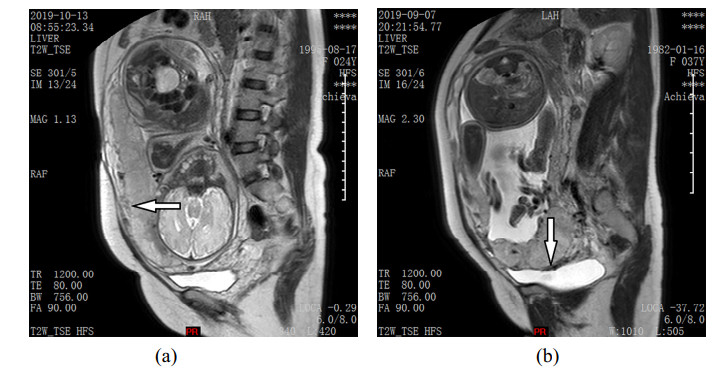

• The purpose of this study was to explore whether the Nomogram, which was constructed by combining the Deep learning and Radiomic features of T2-weighted MR images with Clinical factors (NDRC), could accurately predict placenta invasion. This retrospective study included 72 pregnant women with pathologically confirmed placenta invasion and 40 pregnant women with normal placenta. After 24 gestational weeks, all participants underwent magnetic resonance imaging. The uterus and placenta regions were segmented in magnetic resonance images on sagittal T2WI. Ninety-three radiomics features were extracted from the placenta region, and 128 deep features were extracted from the uterus region using a deep neural network. The least absolute shrinkage and selection operator (LASSO) algorithm was used to filter these 221 features and to form the combined signature. Then the combined signature (CS) and clinical factors were combined to construct a nomogram. The accuracy, sensitivity, specificity and AUC of the nomogram were compared with four machine learning methods. The model NDRC was trained on the dataset of 78 pregnant women in the training cohort. Finally, the model NDRC was compared with four machine learning methods on the independent validation cohort of 34 pregnant women. The results showed that the prediction accuracy, sensitivity, specificity and AUC of the NDRC model were 0.941, 0.952, 0.923 and 0.985 respectively, which outperforms the traditional machine learning methods which rely on radiomics features and deep learning features alone.